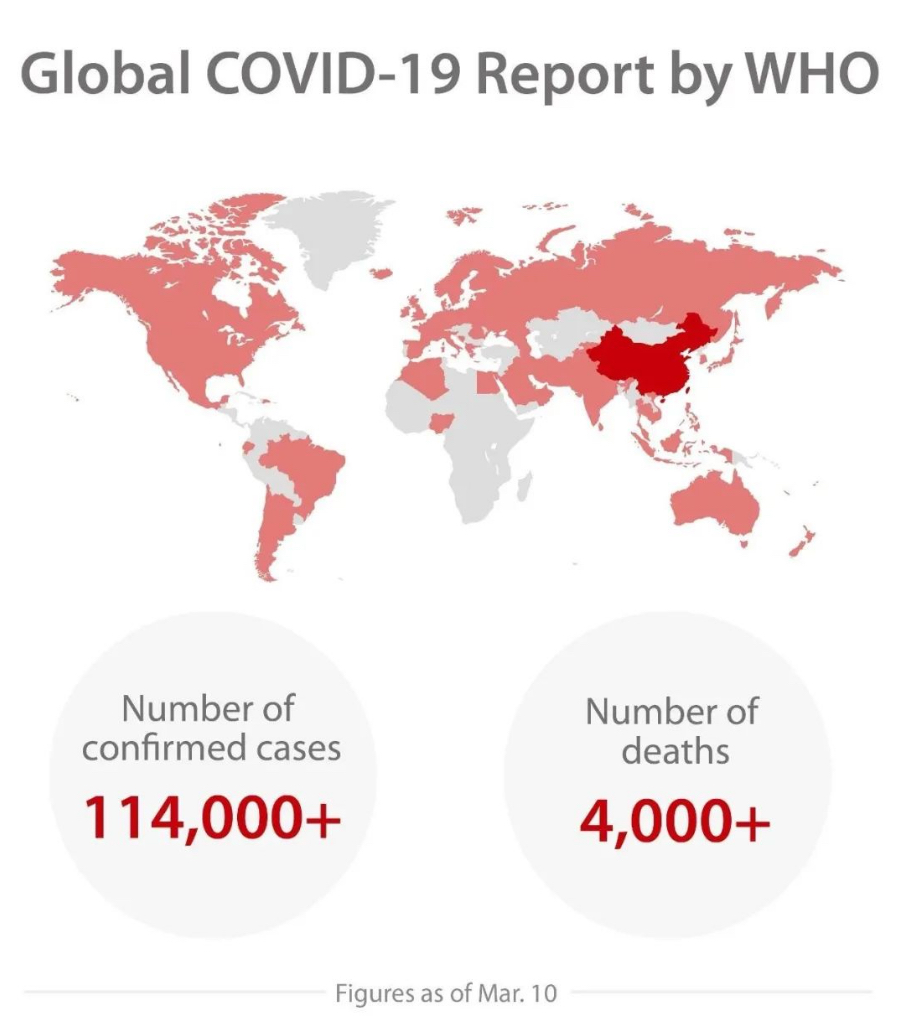

The current outbreak of COVID-19, a dangerous new coronavirus disease caused by the SARS-CoV-2 virus, has spread throughout China and 114 other countries and regions as of March 10. As the epidemic is evolving fast, healthcare workers around the world are racing against time to respond to the outbreak.